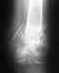

Re: Перелом голени со смещением отломков

• Re: Перелом голени со смещением отломков